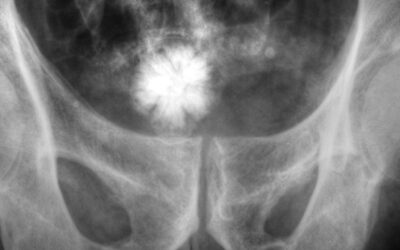

Litiasis vesicular

La vesícula biliar es uno de los órganos que mas suele verse involucrado en trastornos de función y procedimientos quirúrgicos. Esto sucede porque su función principal es la de ayudar al organismo en procesos fundamentales como el metabolismo y la digestión, lo que en...